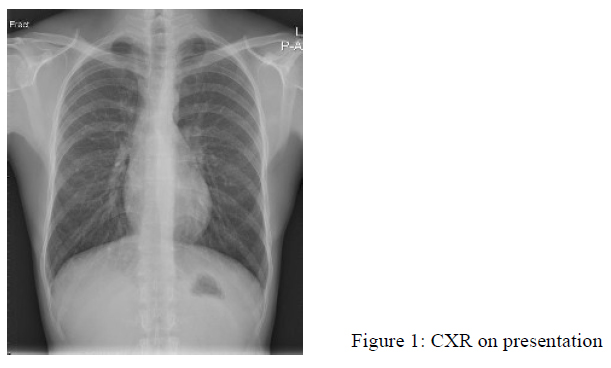

Physical examinations were mostly unremarkable. The blood pressure was normal. Initial blood tests showed Hb 19.5g/dL, Hct 0.56L/L, white blood cell 5.5 x10^9/L, platelet 211 x10^9/L with normal liver and renal function tests. His CXR on presentation was shown in Fig. 1.

The chest radiograph is abnormal in the majority of patients with symptoms attributable to PAVM. The classic chest radiograph appearance of a PAVM is that of a round or oval mass of uniform density, frequently lobulated but sharply defined, more commonly in the lower lobes, and ranging from 1 to 5 cm in diameter. Patients who have multiple PAVM usually have 2 to 8 lesions. Hemorrhage into contiguous parenchyma, or atelectasis may obscure the PAVM shadows in chest radiograph. If patients have microvascular telangiectases, chest radiographs can be normal, or there may be just a vague increase in pulmonary vascular markings at the bases. Sometimes, the chest shadows of PAVM may come and go1.